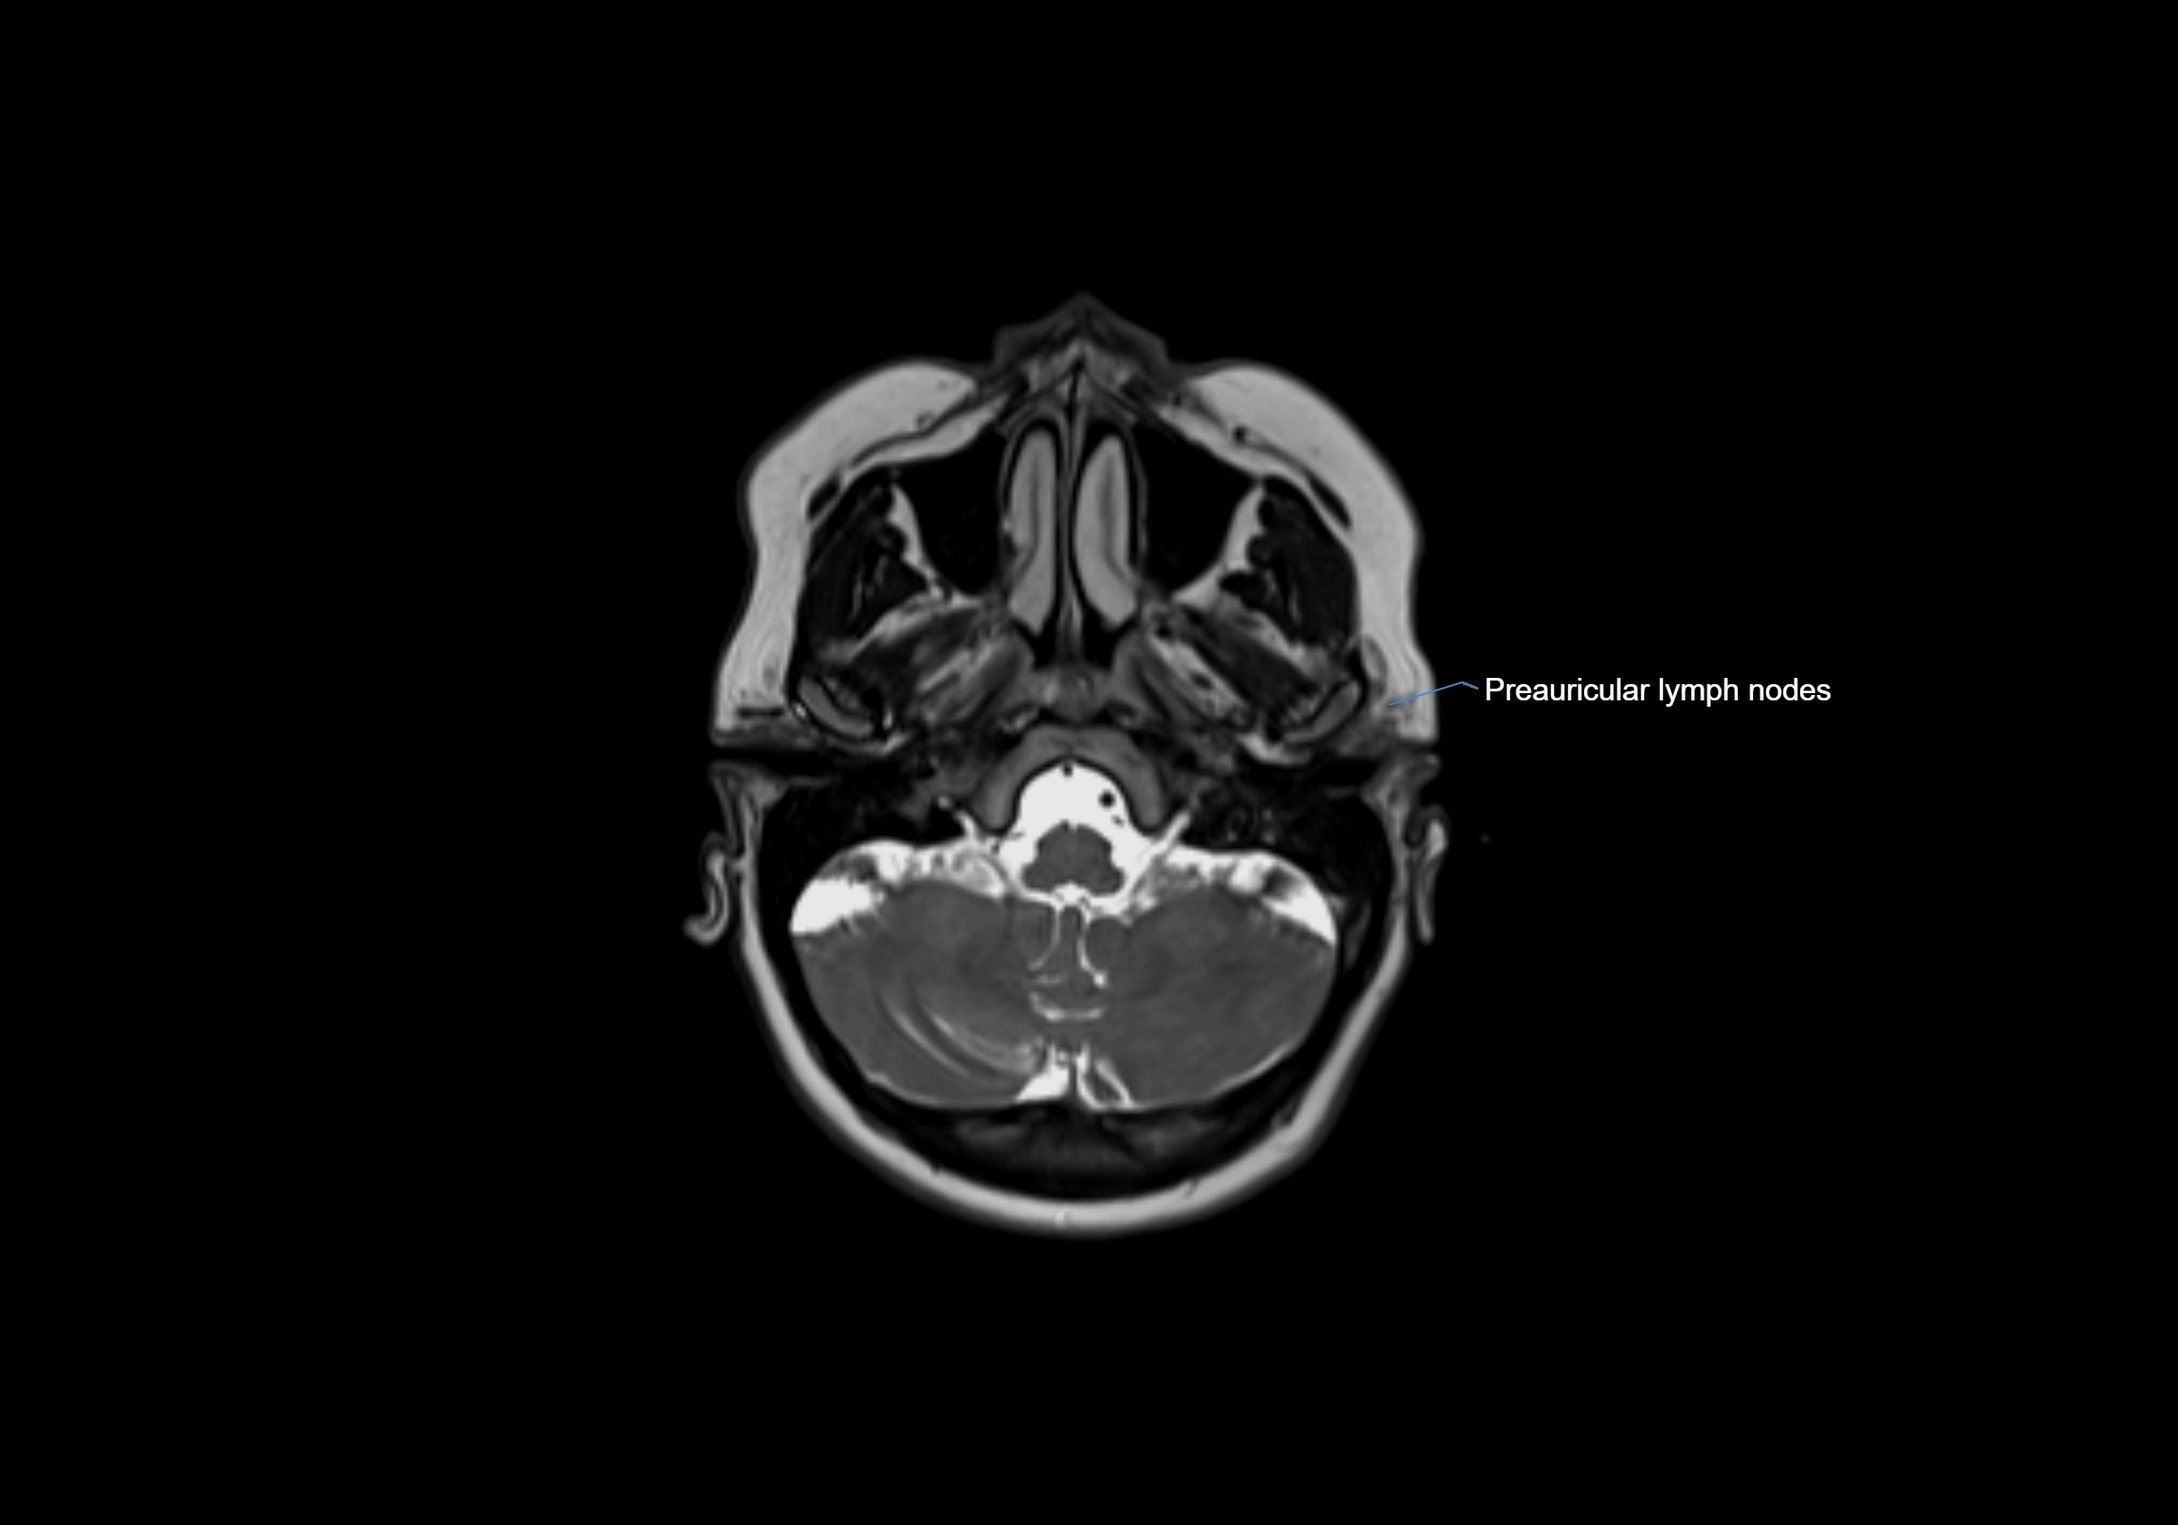

Accessory lymph nodes

Accessory lymph nodes are small, secondary lymph nodes located along the main facial and cervical lymphatic chains, often adjacent to primary lymph nodes, such as preauricular, submandibular, or occipital nodes. They are typically less than 5 mm in diameter, embedded within subcutaneous fat or connective tissue, and may be variable in number and location. These nodes provide additional filtration and immune surveillance for lymph collected from the face, scalp, and neck regions. Accessory lymph nodes are usually non-palpable in healthy individuals but may enlarge in response to infection, inflammation, or metastasis, making them clinically significant.

Location

• Found along primary lymph node chains, including preauricular, submandibular, parotid, and occipital regions

• Embedded in subcutaneous fat or superficial fascia, often lateral or posterior to primary nodes

• Variable in number; may occur unilaterally or bilaterally, depending on individual anatomy

MRI Appearance

T1-weighted images:

• Normal accessory nodes appear as small, oval hypointense to intermediate signal structures within subcutaneous fat

• Surrounded by hyperintense fat, enhancing contrast for visualization

• Pathological nodes may appear enlarged or rounded, sometimes with cortical thickening

T2-weighted images:

• Nodes show intermediate signal, with surrounding fat bright

• Useful for detecting edema, inflammation, or infiltration

• Fatty hilum may appear slightly hyperintense relative to cortex

MRI images

image